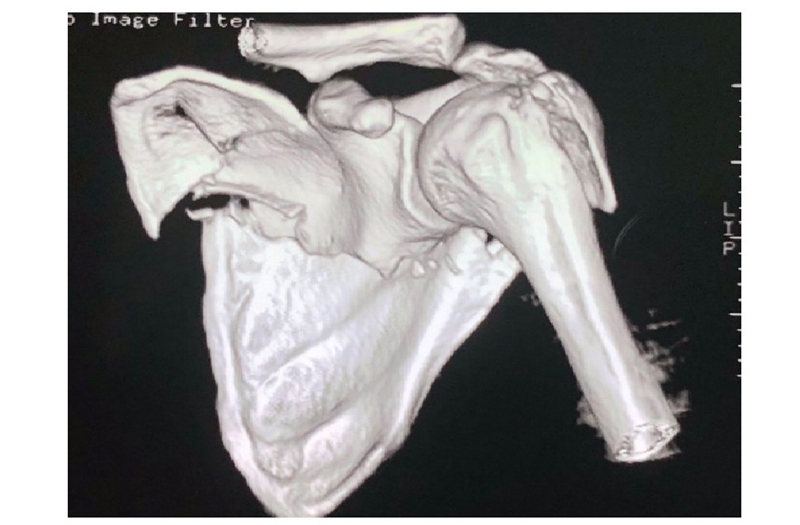

病例5(图23)为患者因车祸导致肩胛骨及肱骨近端骨折,肩胛骨体部骨折块移位显著。

图23 CT三维重建示肱骨近端骨折,肩胛颈及肩胛骨体部骨折